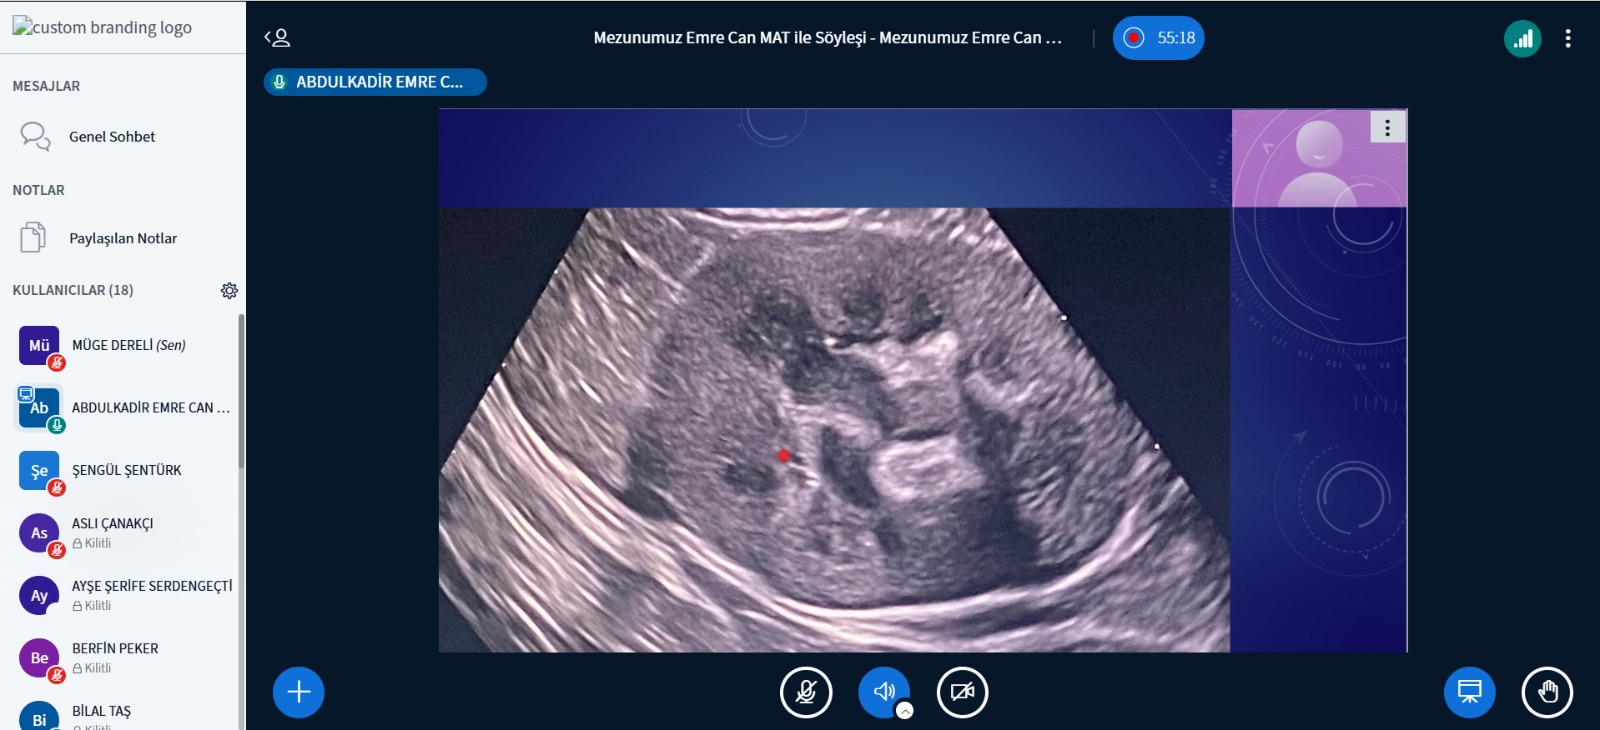

SöyleÅŸide Emre Can Mat, Tıbbi Görüntüleme Teknikleri Programını 1,5 yılda tamamlama sürecini ve bu süreçte edindiÄŸi deneyimleri öÄŸrencilerle paylaÅŸtı. Programların atanma puanları, memuriyet sırasında eÄŸitim olanakları, DGS ile geçiÅŸ imkanları ve öÄŸrencilik sürecinde karşılaÅŸtığı deneyimler hakkında kapsamlı bilgiler aktardı. Ayrıca, Veteriner Fakültesi’nde dersler sırasında elde ettiÄŸi görüntüler ile hastalara ait radyolojik görüntüleri paylaÅŸarak sunumunu zenginleÅŸtirdi ve katılımcıların ilgisini çekti.